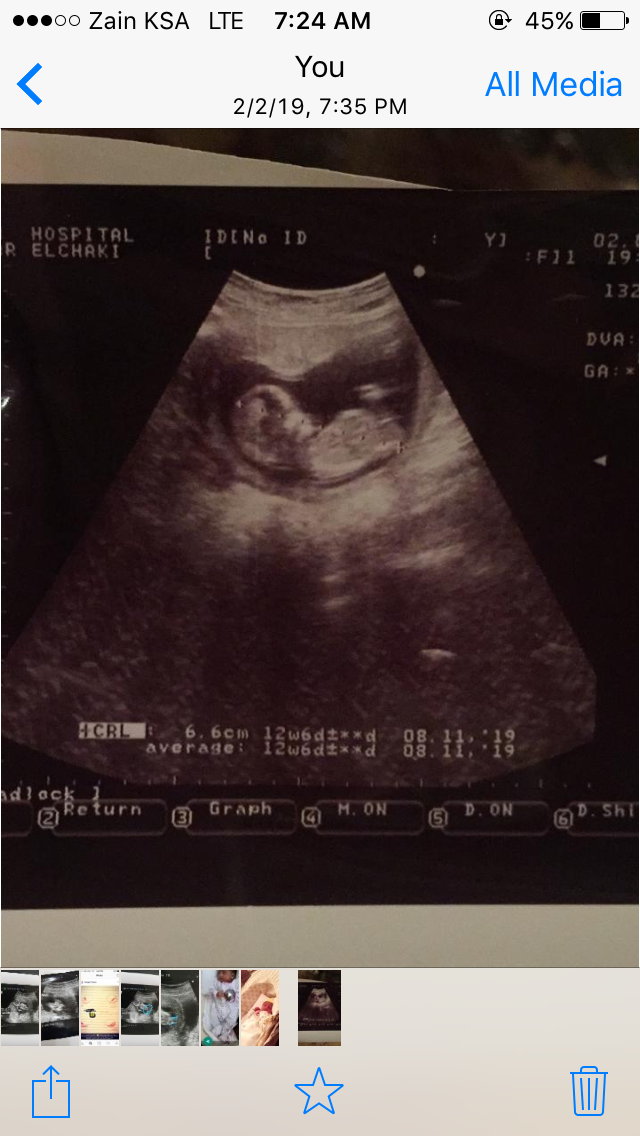

معليش غلطت تاريخ الولاده ١٢/٨/٢٠١٩